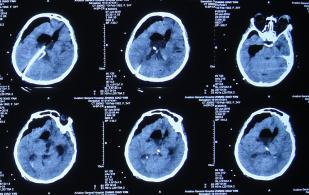

2016年6月3日住入李小勇脑脊液中心,入院时:卧床,反应慢,表情淡漠,言语迟钝(问答无反应),吞咽困难,只能鼻饲流食,头部有多处手术疤痕,右下肢自主活动差,但刺激后能动(图-25);入院第2天即2016年6月5日,头部CT示脑积水,脑室粘连,脑萎缩(图-26)。

图-26:2016年6月5日头部CT入院时

入院后4天即2016年6月7日,进行了脑室腹腔分流管取出术+脑室腹腔分流泵取出术+脑室外引流术+脑室腹壁外引流术+透明隔造瘘术,术后当天查头部CT示脑室引流术后(图-27)。

图-27:2016年6月7日术后头部CT